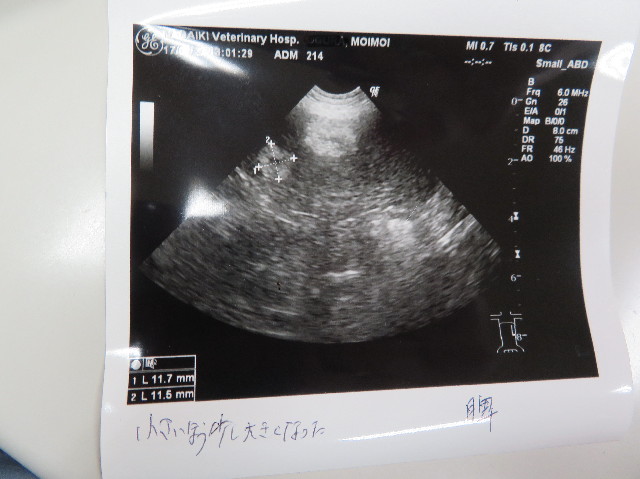

●エコー

○腎臓(左右)問題なし

○膀胱、前からの肥厚あり

○胆のう、前からの胆泥あり

○脾臓、大きいマスはかわりないが、小さいマスが少し大きくなった